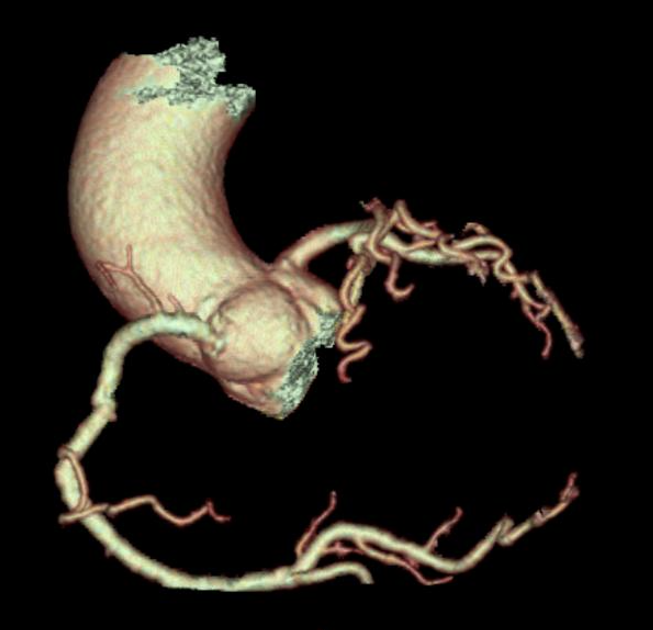

Les images sont reconstruites dans différents plans :- MPR (reconstructions multiplanaires),

- MIP (Maximum Intensity Projection),

- VR (Volume Rendering 3D).

6.1 Anatomie coronarienne

- Origine des artères coronaires (gauche, droite, anomalies d’émergence).

- Trajets des segments proximaux, moyens et distaux.

- Dominance coronaire (droite, gauche ou équilibrée).

- Présence d’anomalies de trajet (intramyocardique, interartériel, etc.).